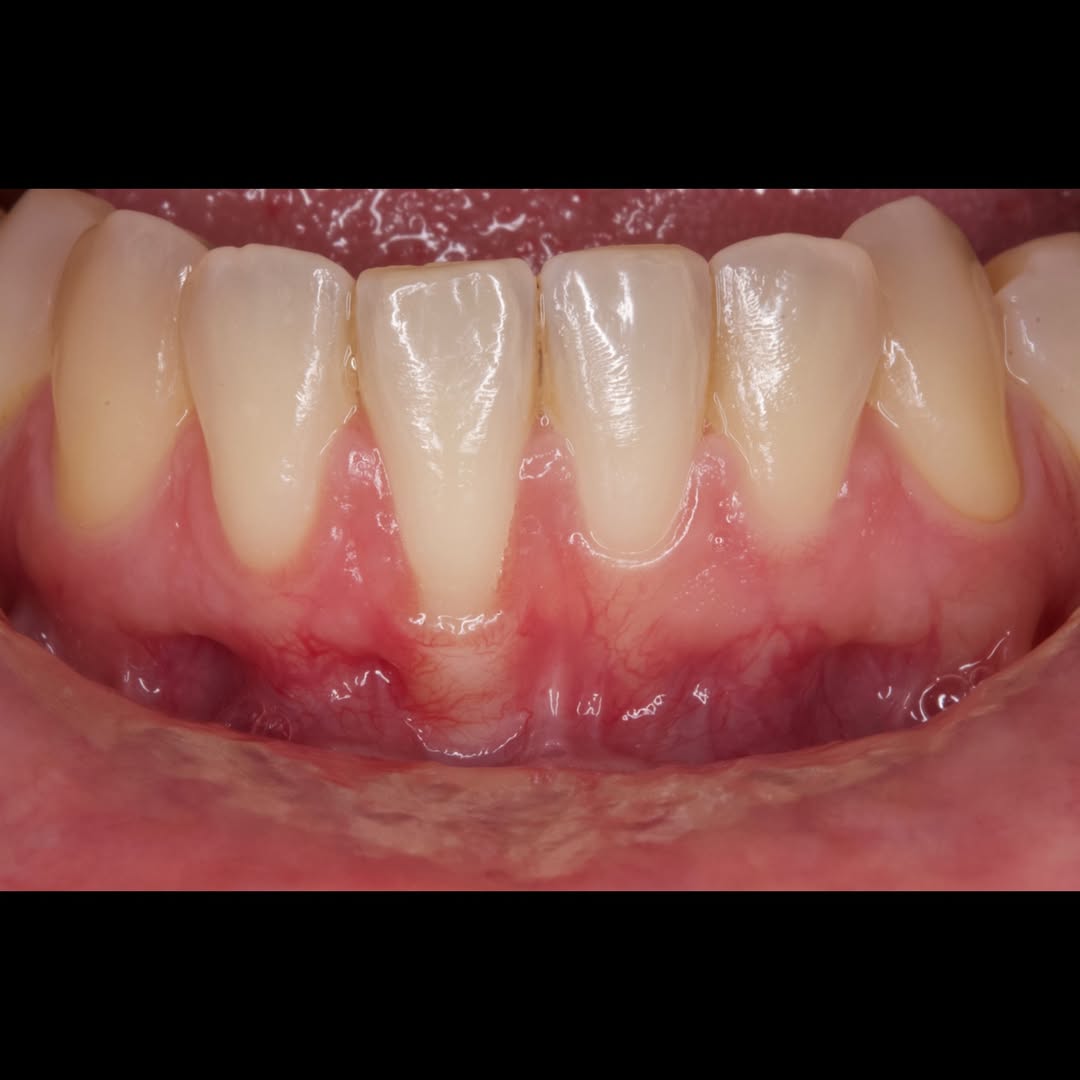

Durante una mañana, asistirás a una Cirugía Mucogingival de recubrimiento radicular de recesiones múltiples en IV y V sextante (36 a 43).

Gracias al uso del microscopio y a la proyección en tiempo real en pantalla, verás exactamente lo mismo que veo yo durante la cirugía, sin tener que estar

Podrás asistir a la planificación de casos y cirugía de injerto de tejido conectivo. Factores determinantes y elección de la técnica adecuada. Sumérgete en un protocolo predecible y técnicamente correcto para obtener resultados óptimos.

Aprende la planificación y técnica de la cirugía Mucogingival para el recubrimiento de recesiones y aumento de banda queratinizada en el sector anteroinferior

Durante una mañana, asistirás a una Cirugía Mucogingival de recubrimiento radicular de una recesión unitaria en 31 con frenillo asociado. Gracias al uso del microscopio y a la proyección en tiempo real en pantalla, verás exactamente lo mismo que veo yo durante la cirugía, sin tener que estar